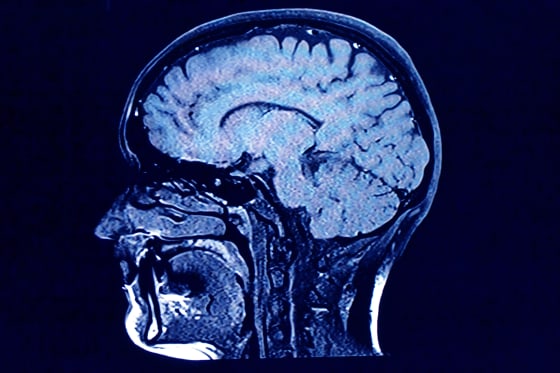

For their research, Mousley and her colleagues analyzed MRI diffusion scans — which are essentially images of how water molecules move within the brain — from about 3,800 people from newborns to age 90. The goal was to map the neural connections across the average person’s brain at different stages in life.

In the brain, the bundles of nerve fibers that transfer signals are encapsulated in fatty tissue called myelin. Think of it like wiring or plumbing. Water molecules diffused in the brain tend to move in the direction of these fibers, rather than across them, meaning researchers can infer where the neural pathways are located.

Based on the MRI scans, the new study maps the neural network of an average person across a lifespan, determining where connections are strengthening or weakening. The five “epochs” it describes are based on the neural connections the researchers observed.